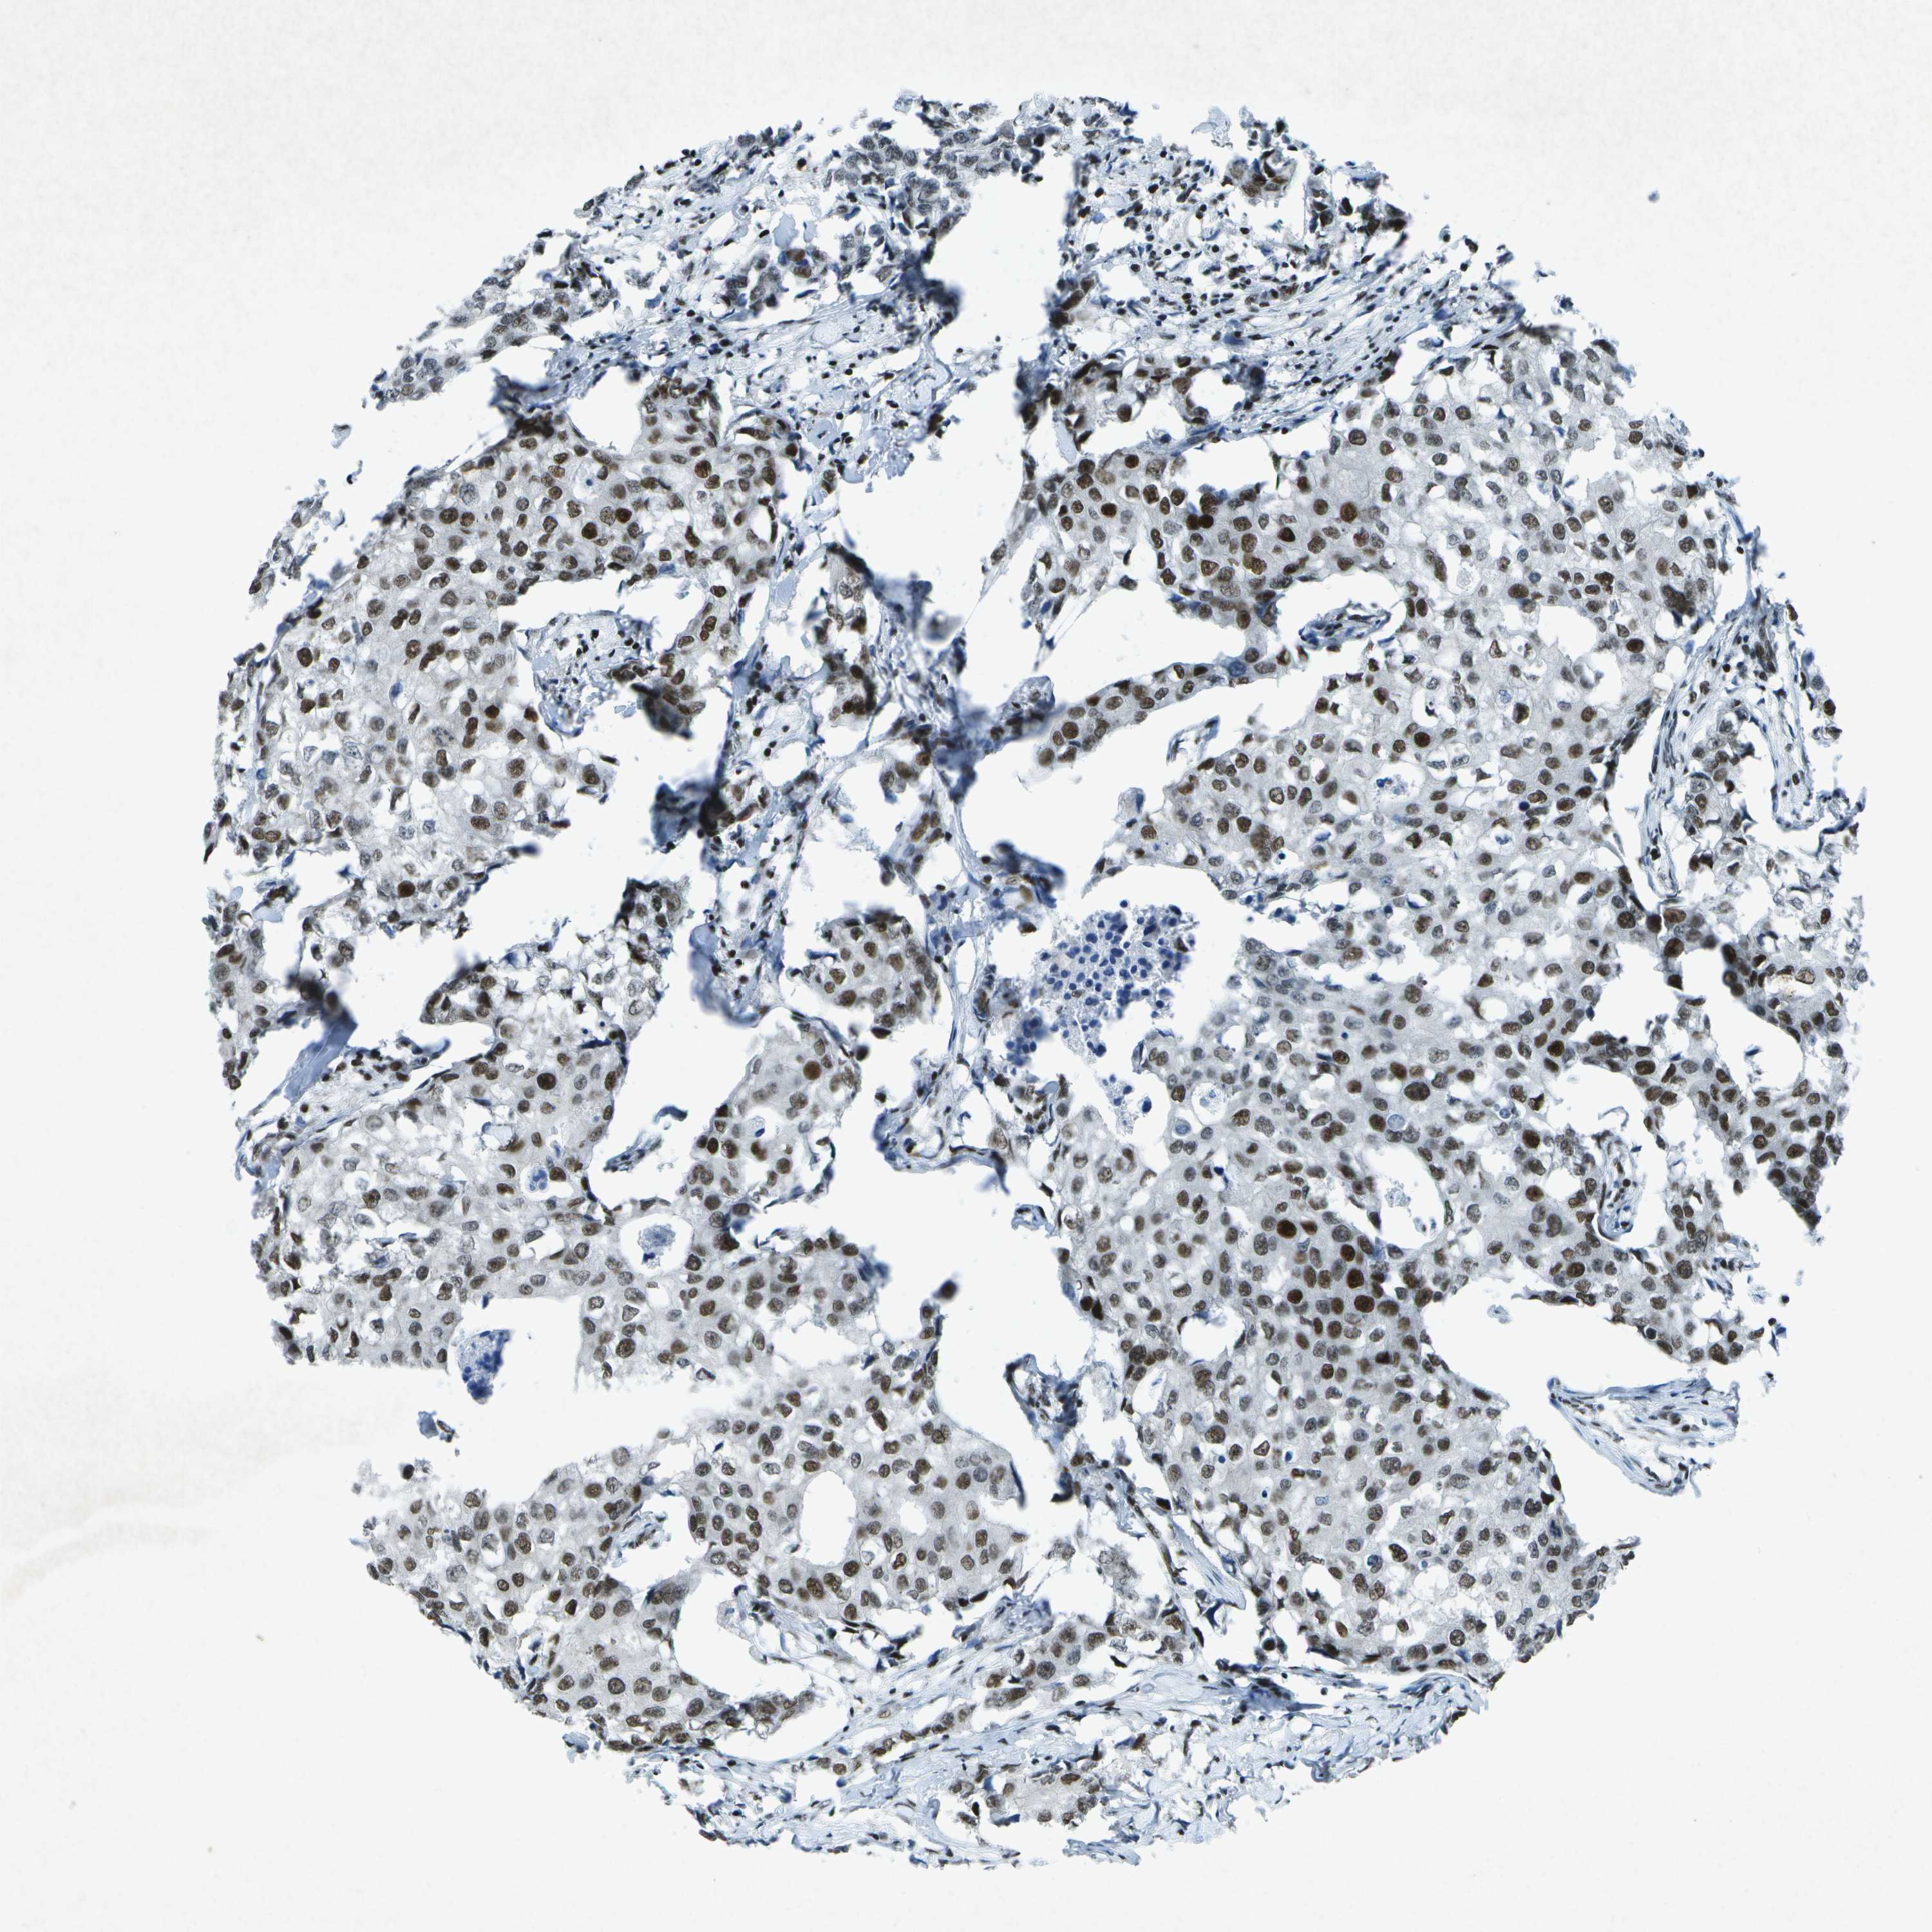

BRCA TCGA BRCA VALIDATION PROTEIN EXPRESSION

ANTIBODIES

AND

VALIDATION